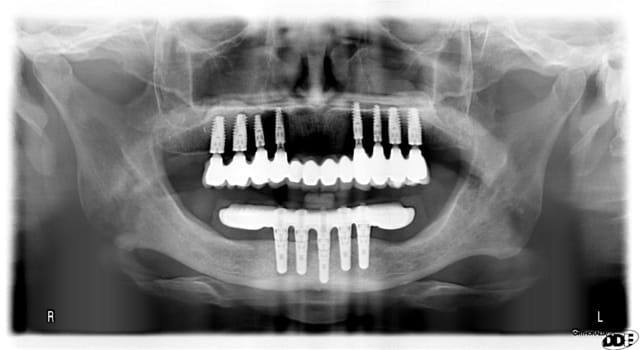

regarde les implants en 13 23 , pour des raisons de conception d'une prothèse transvissée, ils sont posés légèrement en lingual, en dessous de l'os vestibulaire-> la hauteur gingivale est plus importante donc pilier multiunit plus long. je pense que ton cas est exactement le même. tu peut constater que les multiunit sont de longueur différente pour avoir une émergence prothétique de 1mm en sousgingival.